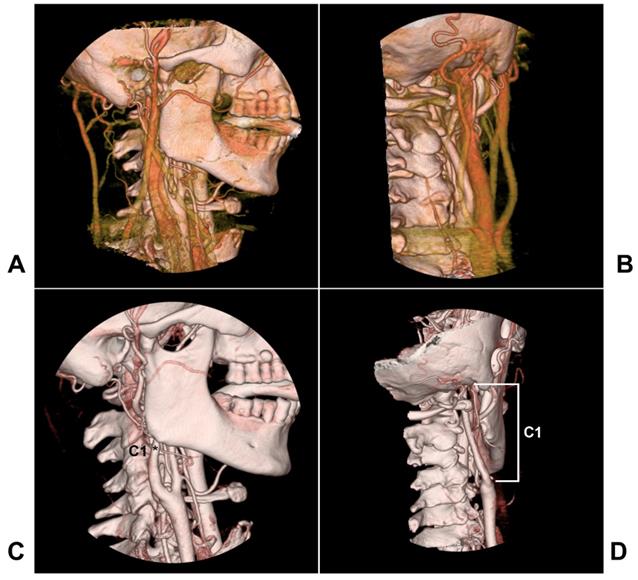

The extracranial internal carotid artery (ICA) refers to the anatomic location from the common carotid artery proximally to the skull base distally, and the segment ICA of the skull base is not included (Figure 1). In 1996, Bouthiller classified the ICA into seven segments: C1, cervical; C2, petrous; C3, lacerum; C4 cavernous; C5, clinoid; C6, ophthalmic; and C7, communicating [1]. This classification is practical and clarifies all segments of the ICA, and the extracranial ICA therefore refers to the C1 segment.

Figure 1

The anatomy of the extracranial ICA region. A-B: Lateral view (A) and posterior anterior view (B) of CTA showing carotid veins around the extracranial ICA. C-D: Lateral view (C) and posterior anterior view (D) of CTA showing that the extracranial ICA extends from the bifurcation to the skull base, and the extracranial ICA belongs to the C1 segment of the Bouthiller classification (asterisk). Abbreviations: CTA: computed tomography angiography; ICA: internal carotid artery